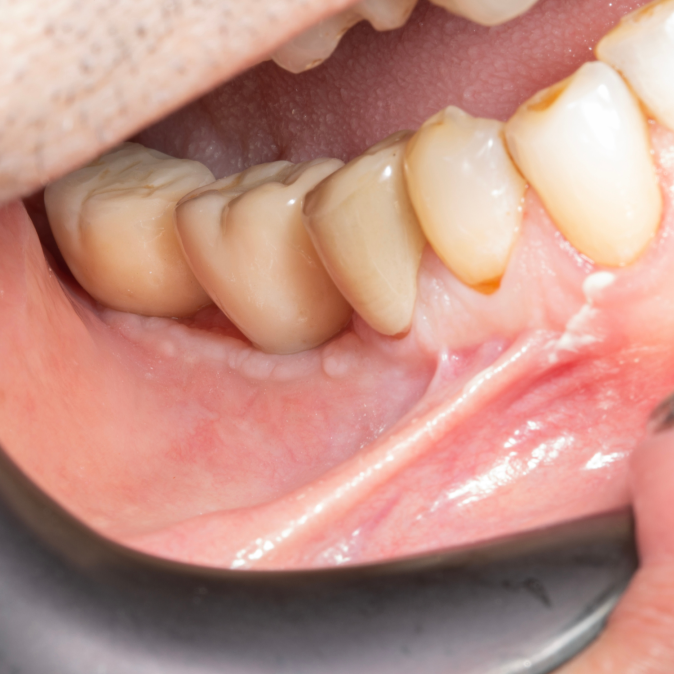

İmplant etrafındaki kemik açıklığını kemik grefti ile tedavi ettiğimiz vakamız.